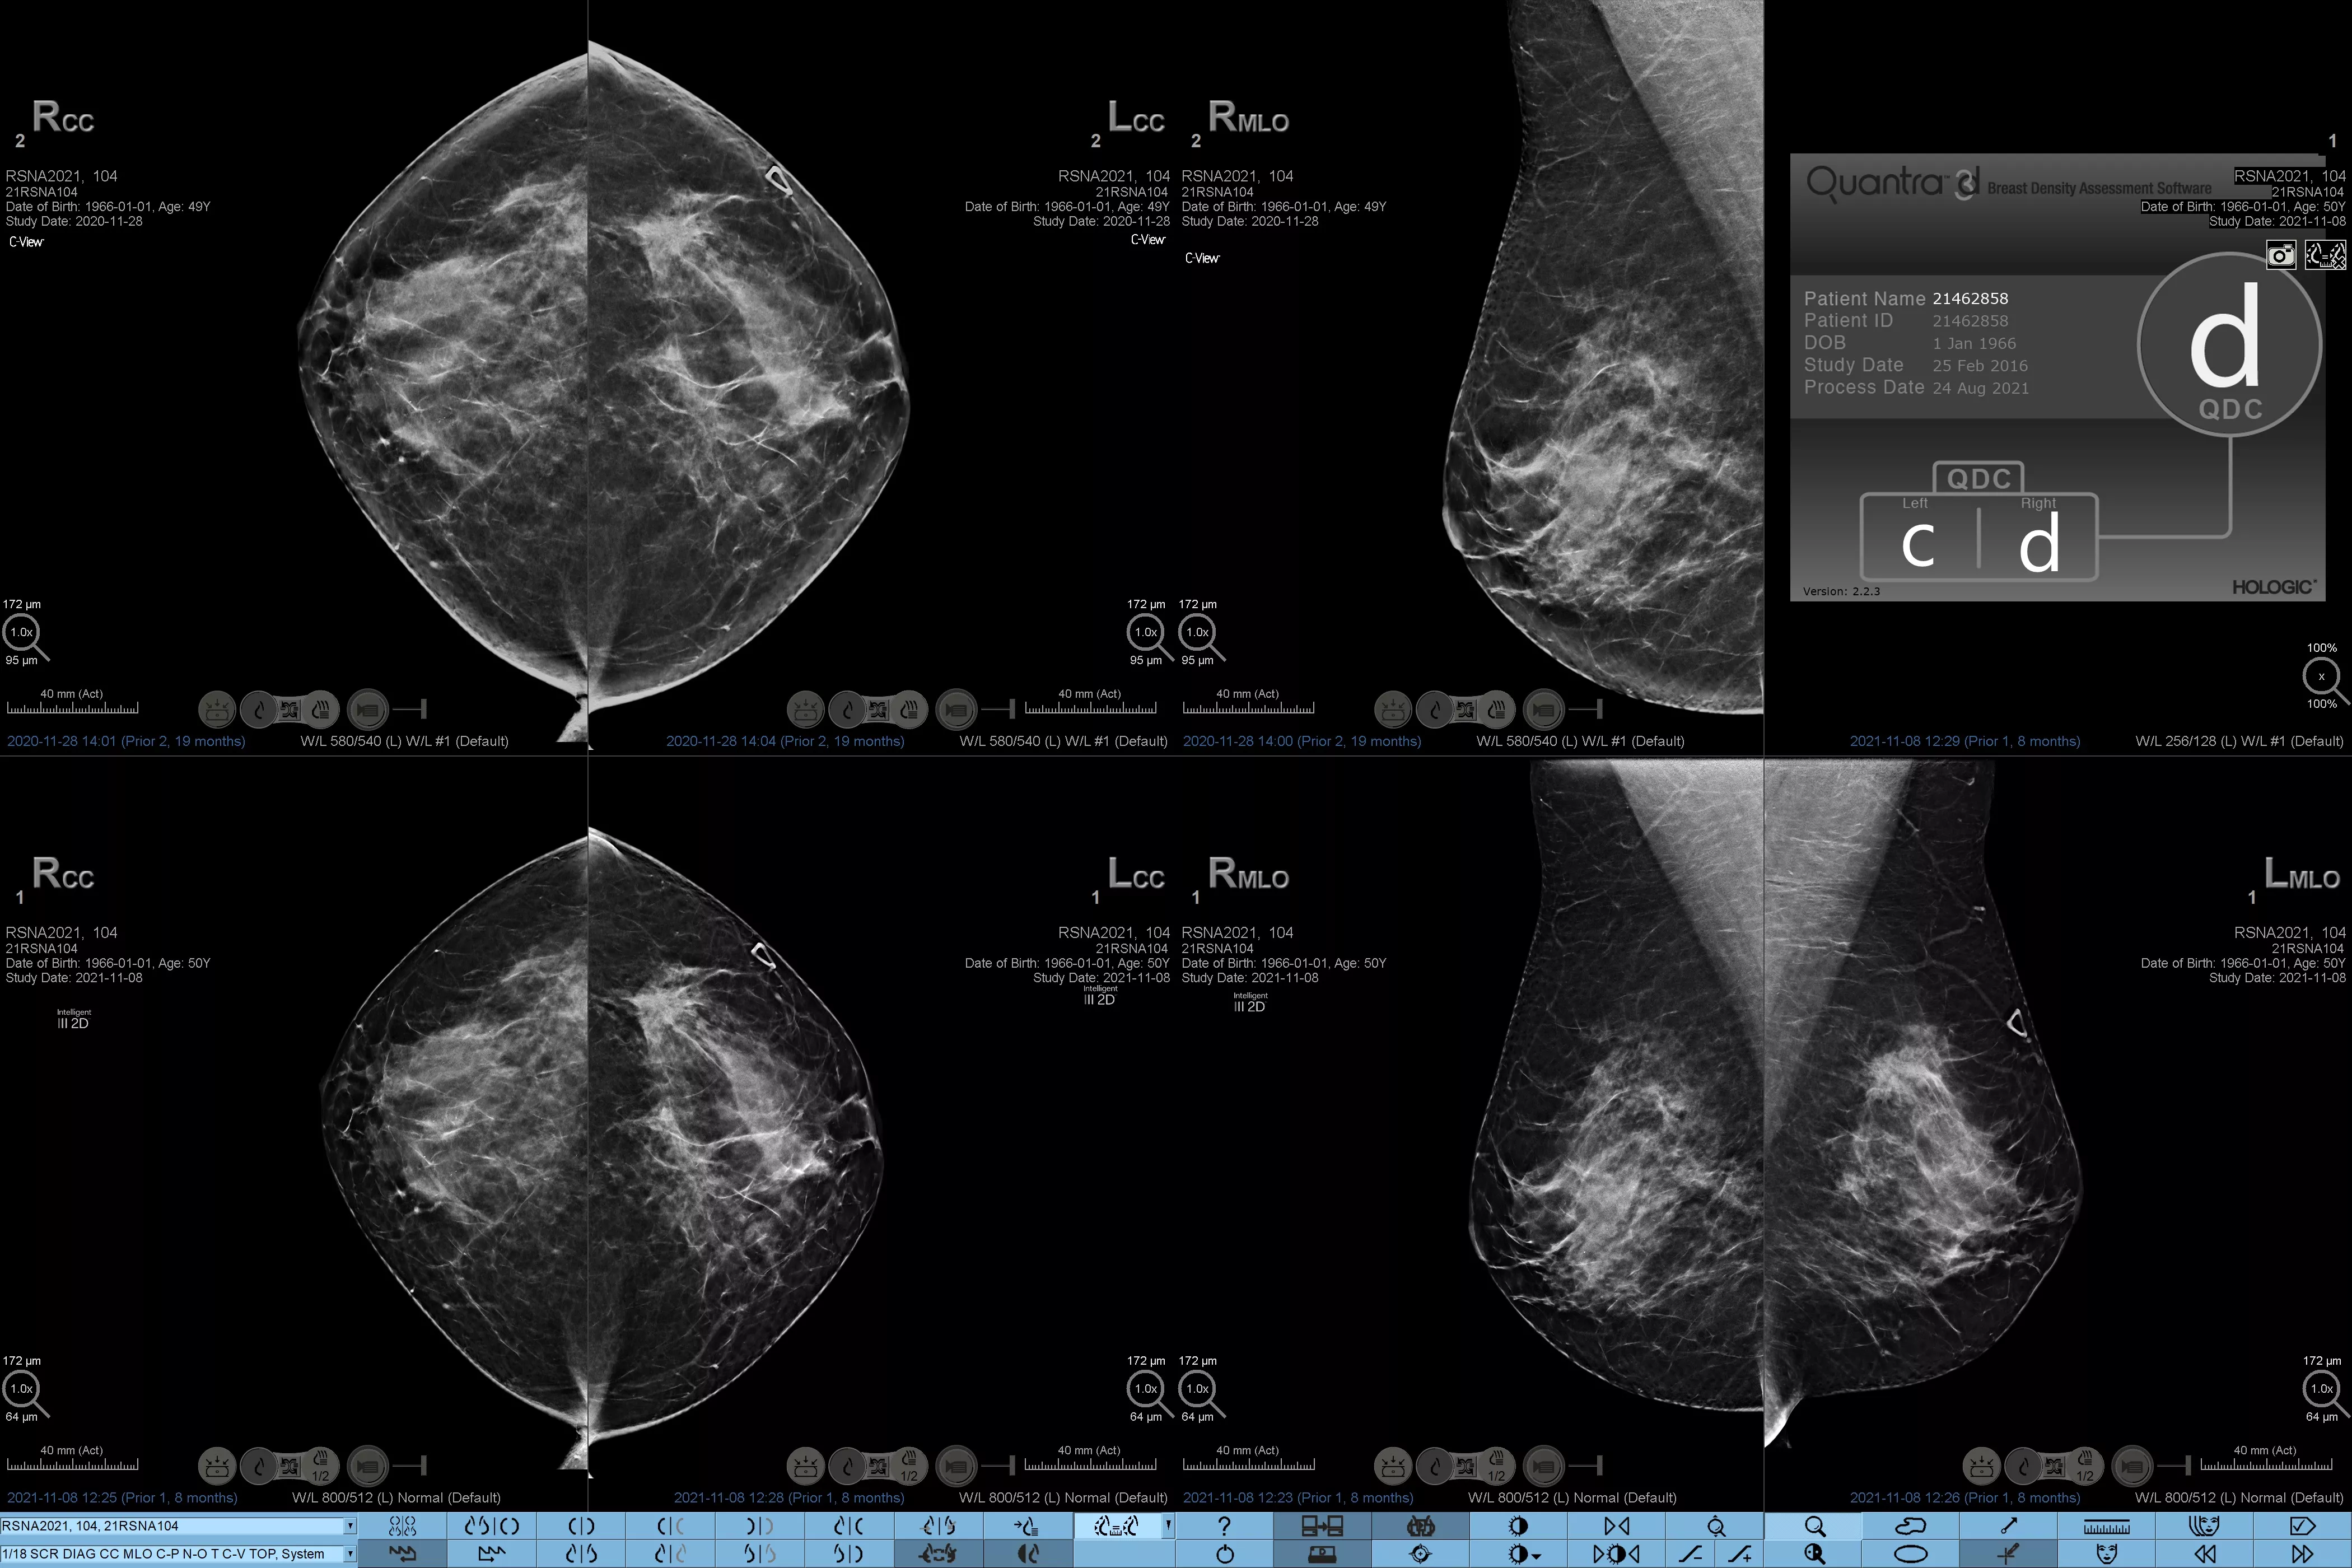

Higher breast density is known to increase a woman’s risk for breast cancer.1 The need for accurate, unbiased analysis is therefore critical. Powered by machine learning, Quantra technology software analyses both 2D™ and tomosynthesis images for distribution and texture of parenchymal tissue. It categorises breasts in four breast composition categories consistent with guidance from the American College of Radiology (ACR) BI-RADS Atlas 5th Edition.2

Objective machine learning algorithm that assigns breast density category based on analysis of breast tissue texture and patterns.